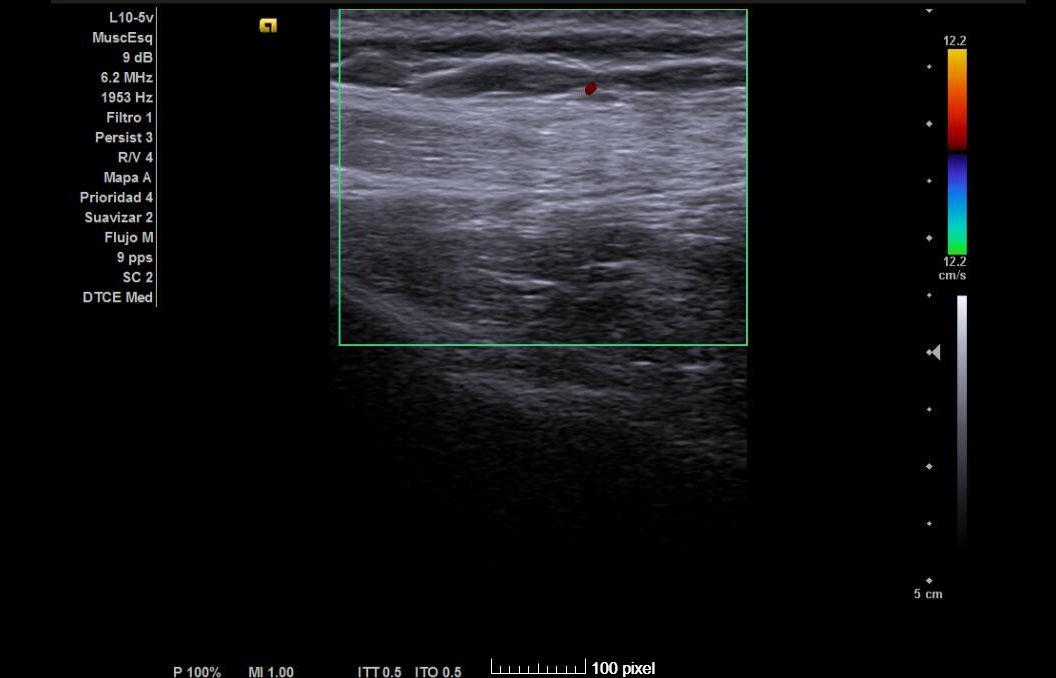

Hallazgos ecográficos

Tendones supra e infraespinoso normales; bursa fina; cabeza larga del bíceps normal. Nervio supraescapular discretamente hipoecoico y engrosado en la escotadura; sin colecciones. Sin signos de pinzamiento dinámico.